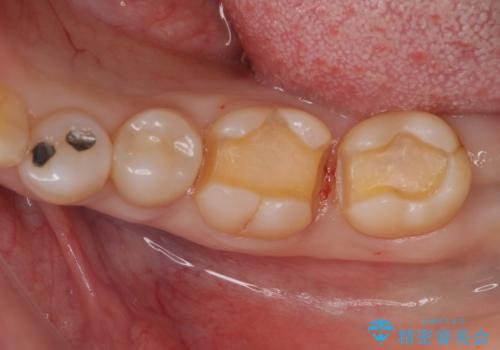

アマルガムを除去 虫歯を除去して、セラミックのつめものに

- 劣化したプラスチックとアマルガムをはずしてセラミックにしていく治療を行いました。

アマルガムは水銀が含まれている為、外したい方が増えています。

①初回 アマルガム、古い詰め物の除去、虫歯の除去